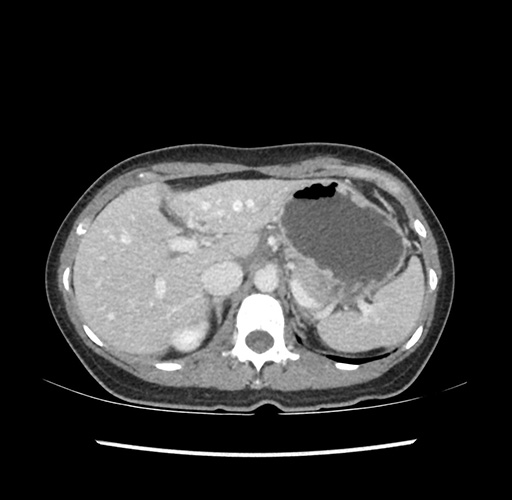

Imaging Analysis

Look through the patient's CT scan to identify any areas of concern for the necessary procedure.

Based on your CT findings, which issue(s) would give reason for "planned slowing down moment(s)" in this case?